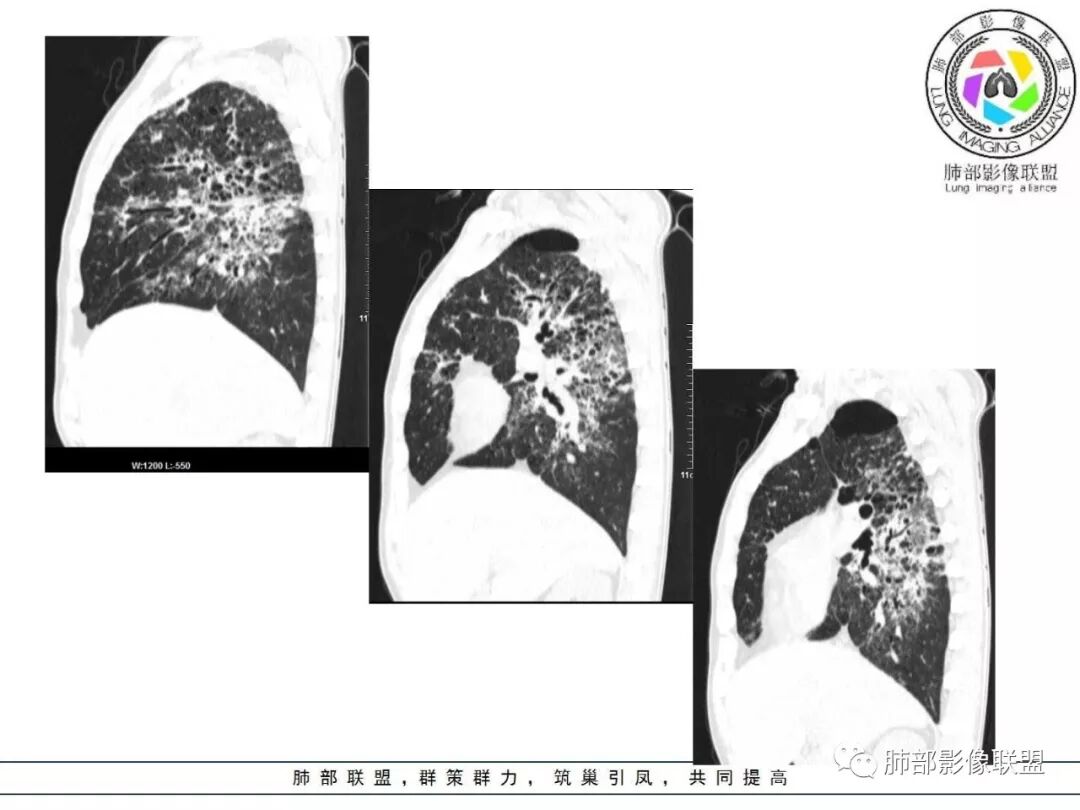

答案揭晓

间质性肺结核

间质性肺结核是结核的一种特殊影像学表现,为继发性肺结核,影像学表现与常见的继发性肺结核有所不同,有一定的特征性:

病灶呈片状磨玻璃密度影,呈典型的烟花征。磨玻璃影密度偏高,有网结节样改变,与正常肺实质分界清楚,且常见相对高密度的勾画。

烟花征分为3肿类型:晕征、反晕征及均匀分布。

病变一般沿血管支气管束分布或小叶分布,一般上肺多于下肺(这与常见继发性肺结核分布相若)。

常会伴有其他继发性肺结核病灶,如斑片影、结节影,树芽征,新旧不等改变。

临床中毒症状常较轻,病变相对稳定,增强扫描常无异常强化。